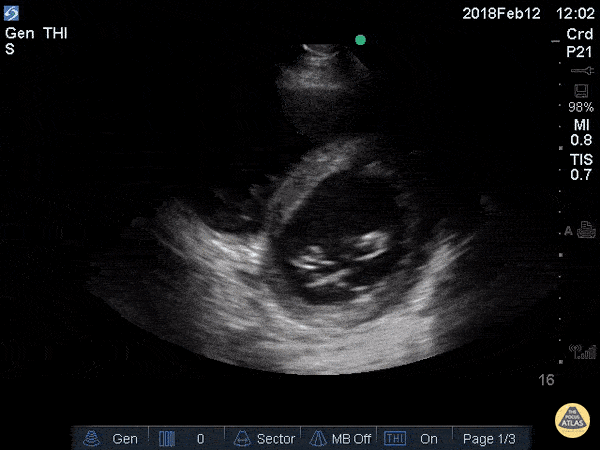

Apical 4 Chamber

• ANATOMIC LANDMARK: apex (5th interspace, ant ax line)

• Probe marker to the right

• SONOGRAPHIC LANDMARK: HEART

• Identify: LV, RV, LA,, RA, MV, TV

• Pericardium +/- Pericardial fluid